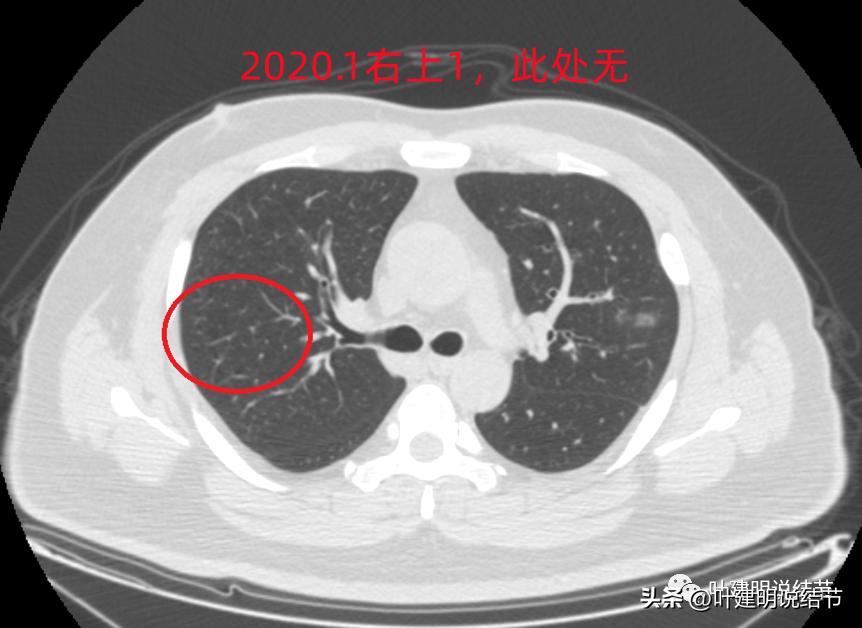

2020年时同样位置是没有异常的:

还敢判定右上的病灶是恶性范围的不典型增生或原位癌吗?我是连左上病灶4都不敢了!还好,我觉得我们不必去纠结这几个病灶到底是不是肺癌或腺体前驱病变,反正至少风险很低,能随访就是了,肯定不能建议手术或消融等干预,也不需要穿刺活检。只要仍继续随访,半年吧!将结果交给时间来判断。